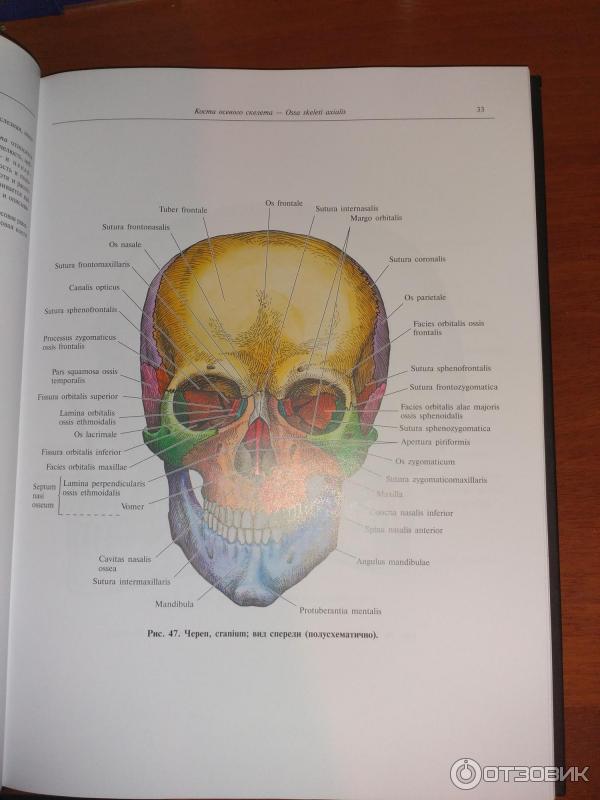

Анатомические детали: Фотографии топографии черепа с нижнего вида

Раздел: Альбом идей